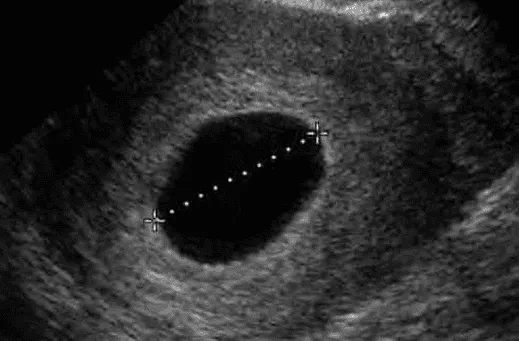

- Chiều dài từ đỉnh đầu đến mông (CRL) ≥ 7 mm mà không có tim thai.

- Đường kính túi trung bình (MSD) ≥ 25 mm mà không có phôi thai.

Tiêu chuẩn rõ nhất là CRL ≥ 7 mm không thấy tim thai. Nếu CRL < 7 mm và không thấy tim, phải chờ tái siêu âm.

Để chẩn đoán trứng trống, không đủ khi chỉ không thấy phôi hoặc túi noãn hoàng với MSD < 25 mm. Phải có MSD ≥ 25 mm không thấy phôi hoặc túi noãn hoàng.

- CRL ≥ 7 mm không thấy tim thai.

- MSD ≥ 25 mm không thấy phôi thai.